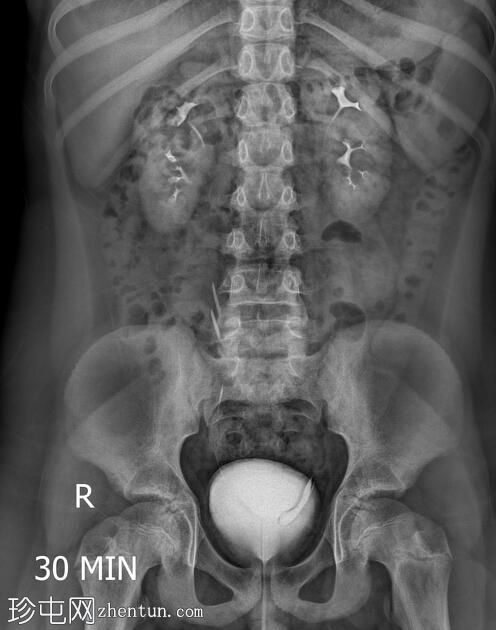

年龄:11岁

性别:男

透视检查

双侧肾盂肾盏系统及输尿管重复畸形。

左肾上极异位输尿管末端形成输尿管囊肿。

根据魏格特-迈耶定律,在完全性输尿管重复畸形的双肾病例中,上极和下极分别由独立的输尿管引流。上极输尿管通常存在异位开口,位于下极输尿管的内侧和下方,并常形成输尿管囊肿,正如本病例所示。